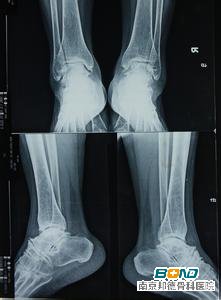

踝关节骨质增生的治疗方法

骨质增生(增生性骨关节病)是指由于关节退行性变,以致关节软骨被破坏而引起的慢性关节病。又称退化性关节炎、骨关节炎及肥大性关节炎等。